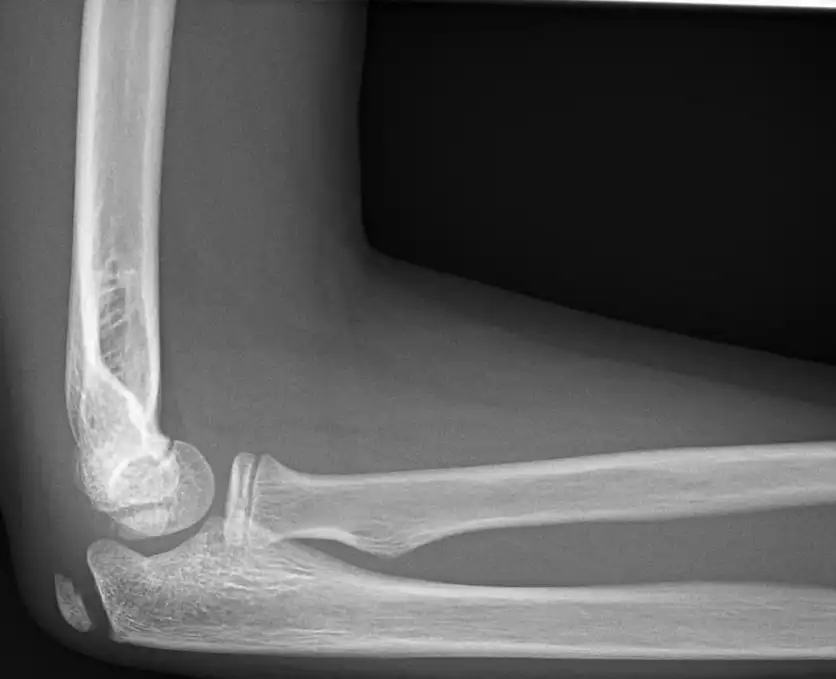

تشخیص بورسیت اولکرانون معمولا با معاینه فیزیکی دقیق آرنج توسط پزشک متخصص ارتوپدی صورت میگیرد. پزشک با لمس ناحیهی آرنج، بررسی تورم، درد و محدودیت حرکتی میتواند به تشخیص اولیه برسد. در برخی موارد، پزشک ممکن است برای تایید تشخیص و بررسی دقیقتر، درخواست انجام آزمایشاتی نظیر رادیوگرافی یا سونوگرافی آرنج بدهد.

اشعه ایکس: برای رد شکستگی یا سایر مشکلات استخوانی